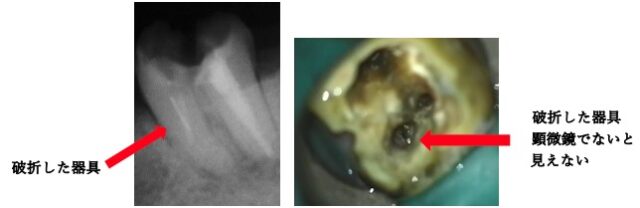

ケース③:根の中に「折れた器具」が残っている歯

【治療前】

過去の治療で使用した金属製のヤスリ(ファイル)が、治療中に折れて根の中に食い込んでしまっているケースです。この「破折器具」が邪魔をして、その先の掃除ができないため、感染が治りません。肉眼ではその存在すら確認できないことが多く、除去は極めて困難(最難関)とされています。

【マイクロスコープ治療】

マイクロスコープで高倍率に拡大し、破折した器具の頭を確認。特殊な超音波器具を用いて、周りの歯を削りすぎないように慎重に振動を与え、器具を除去することに成功しました。